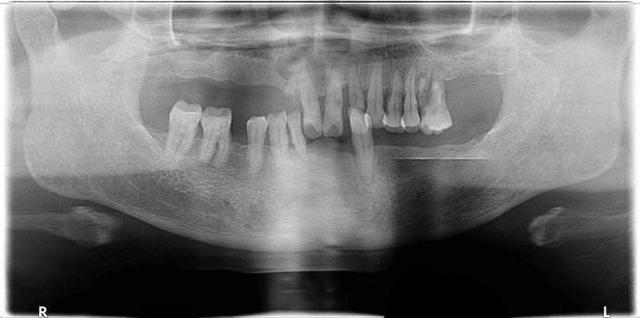

3、廢用性:用進廢退,這是很多人都明白的道理,一般老年人沒有了牙齒後,牙齦和牙槽骨沒有足夠的刺激,就會(hui) 導致牙齦萎縮,牙槽骨吸收的情況。因此,建議牙齒缺失後及時鑲牙修複,否則不僅(jin) 難度增加,而且不能享受晚年幸福生活。